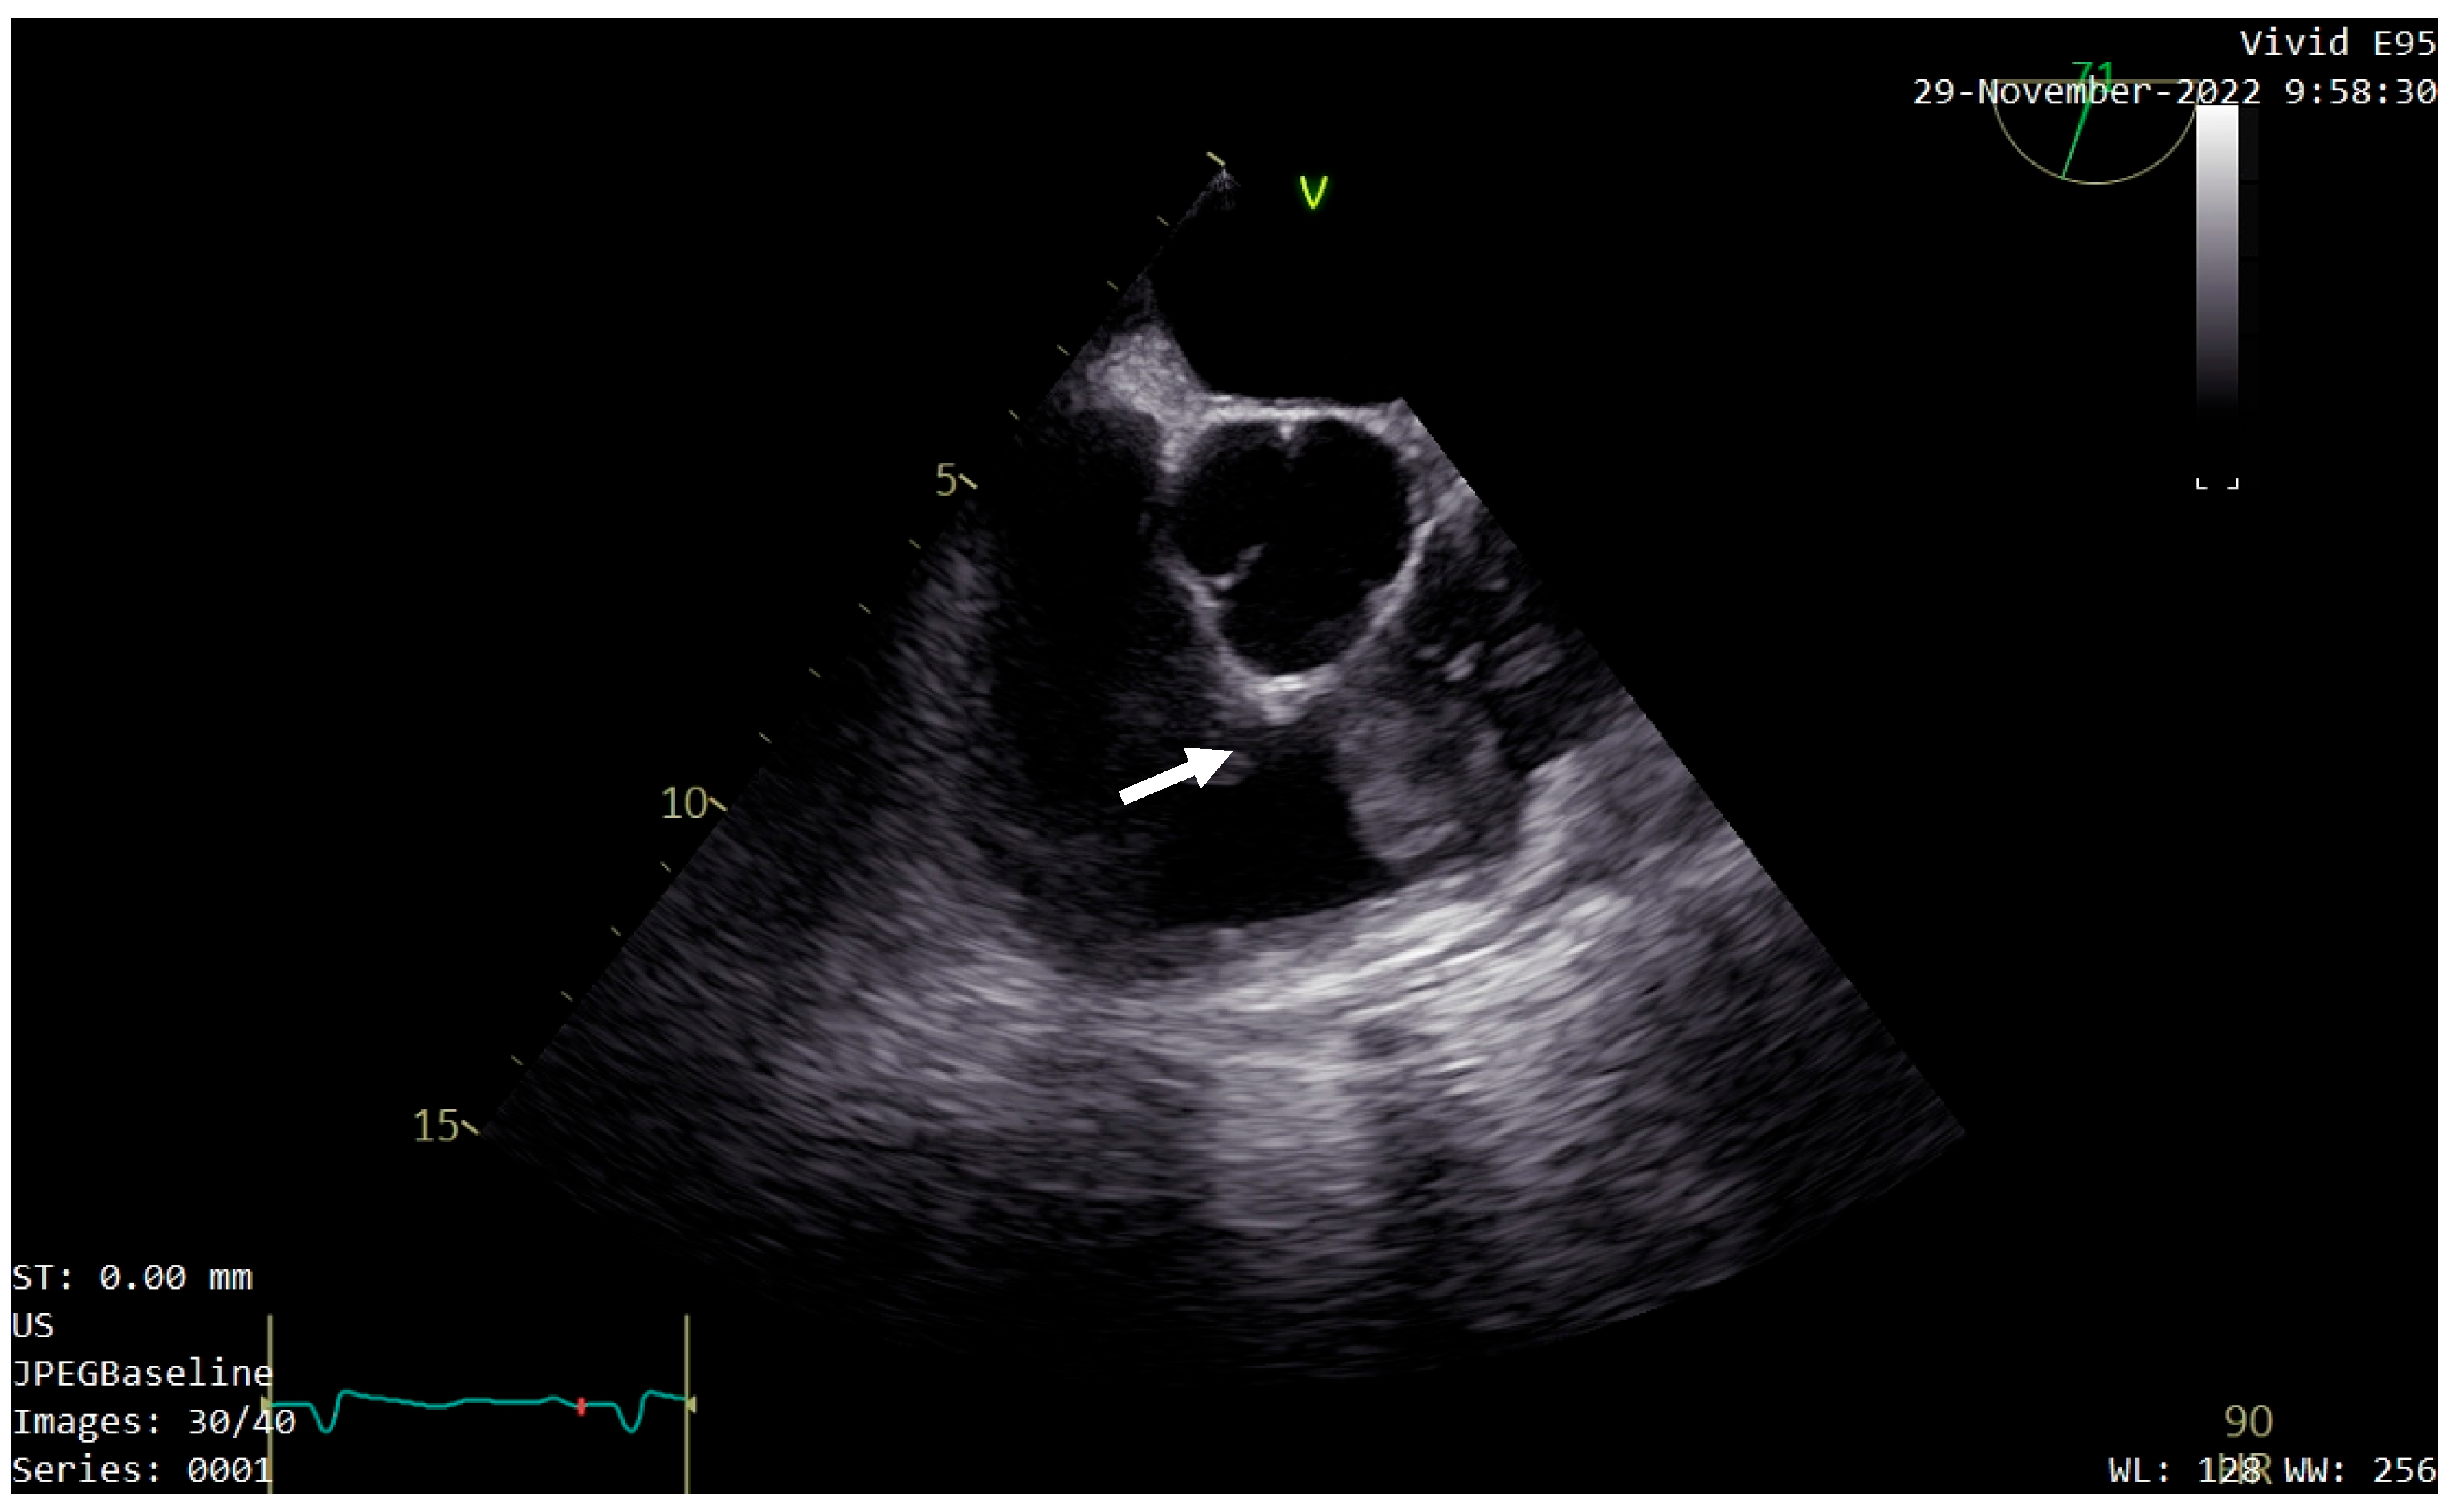

A transthoracic echocardiography (TTE) was performed. It showed a round 25/30 mm, 6.5 cm2 intracardiac mass attached to the right ventricle outflow tract (RVOT) wall by a 5 mm thick pedunculus (Figure 1a), which prolabated through the pulmonary valve in systole, thus causing severe obstruction at this level with a maximum gradient of 70 mmHg (Figure 1b and Figure 2). The pulmonary valve itself presented no structural abnormalities, but the right ventricle was dilated (50 mm at the base) with a slightly decreased systolic function (TAPSE = 15 mm), a moderate tricuspid regurgitation and paradoxical interventricular septum motion being also observed due to right ventricular pressure overload. The left ventricle was not dilated and had a preserved systolic function, and only a mild mitral regurgitation was noted.

Figure 1. Transthoracic echocardiography (TTE) showing: (a) a round intracardiac mass attached to the right ventricle outflow tract (RVOT) wall by a pedunculus (white arrow); (b) turbulent flow on Color Doppler caused by the tumor’s severe obstruction of the RVOT (white arrow).